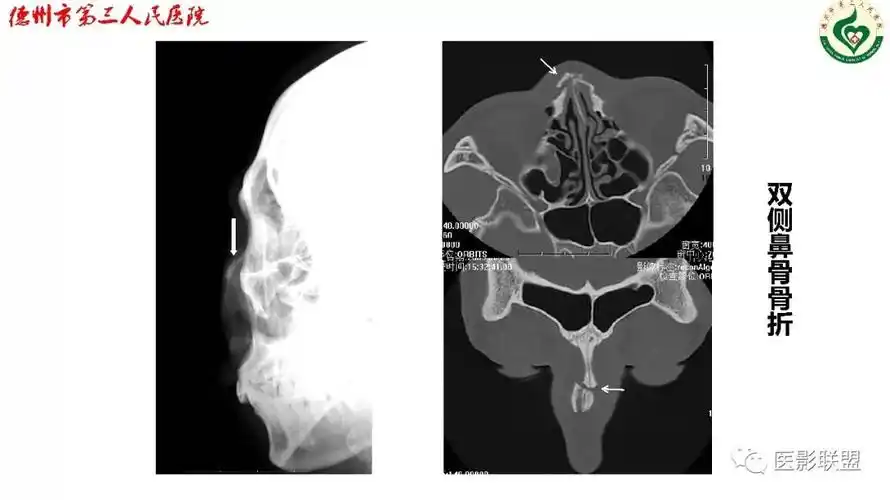

清晰图讲解鼻骨骨折影像学诊断